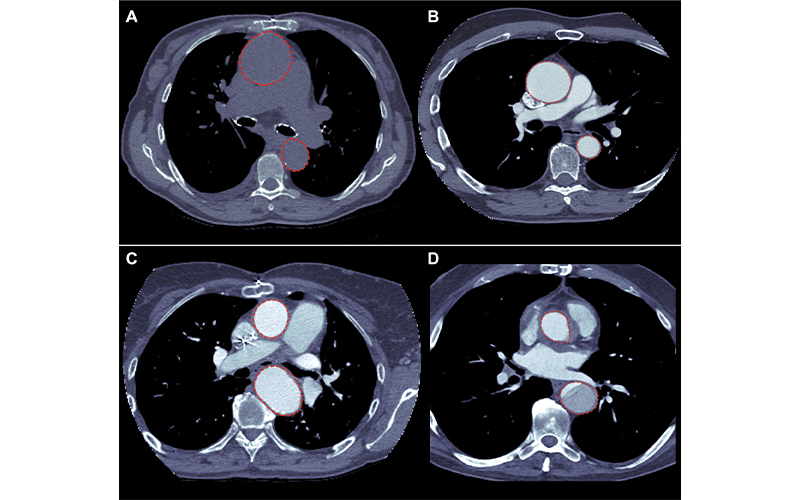

Images of the artificial intelligence model segmentation output (red circles) overlaying the (A) axial CT images of a non–contrast-enhanced CT study with an aneurysm in the ascending aorta, (B) a contrast-enhanced CT study with an aneurysm in the ascending aorta, (C) a contrast-enhanced CT with an aneurysm in the ascending aorta, and (D) a contrast-enhanced CT with dissection in the descending aorta. https://doi.org/10.1148/ryai.210076 ©RSNA 2022